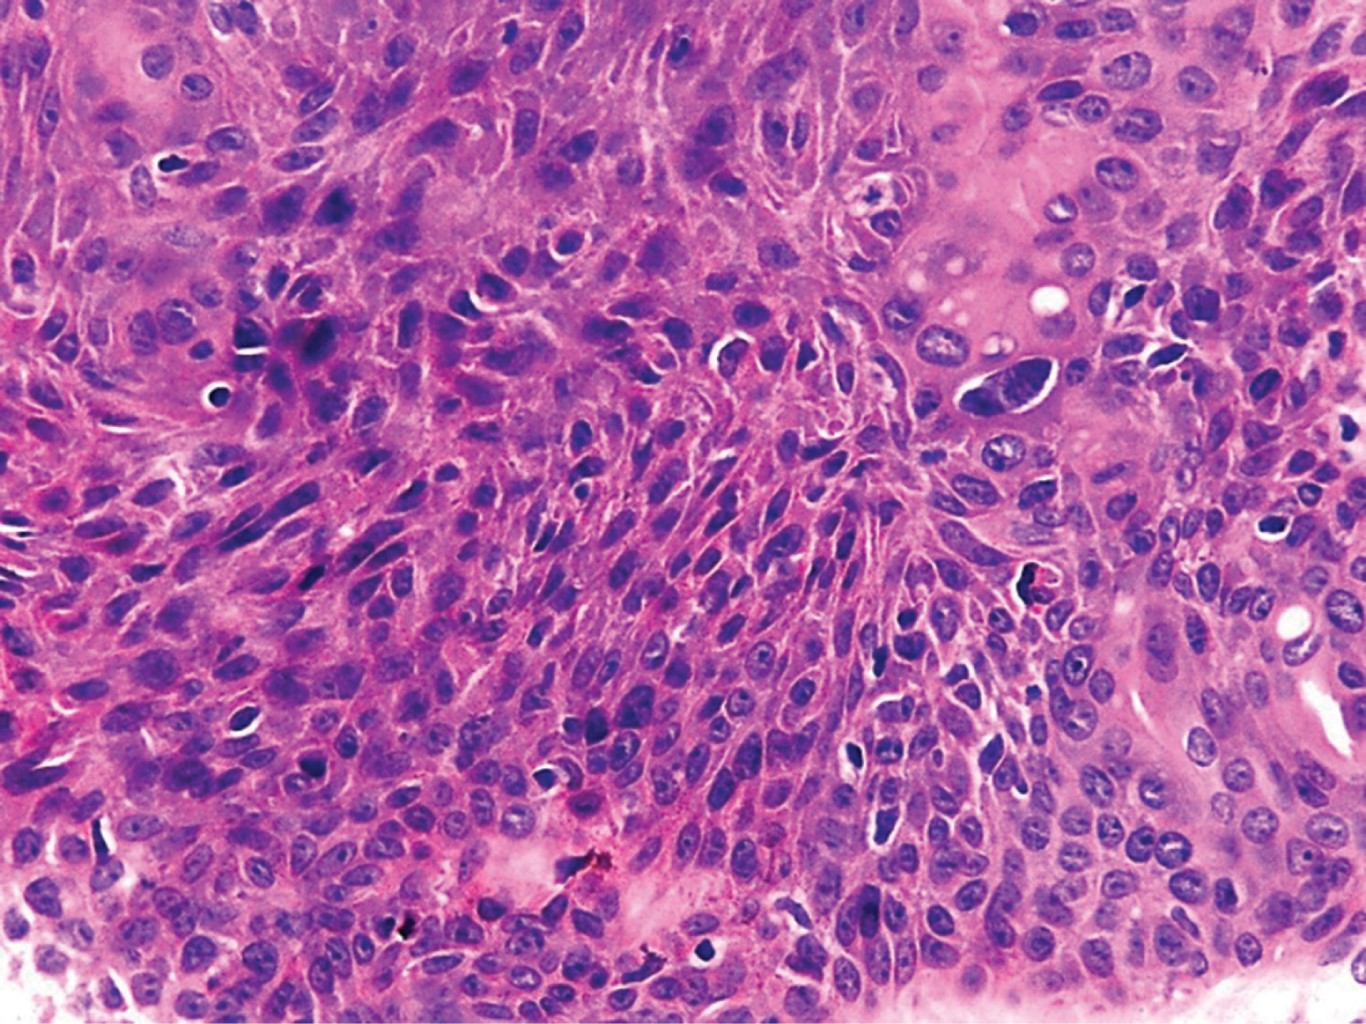

Con la sospecha clínica de probable poroma ecrino se realiza biopsia excisional. El estudio histopatológico reporta neoformación Exofítica, cuya epidermis muestra hiperqueratosis paraqueratósica (Figura 3). En todo el espesor de la dermis se observan cordones tumorales conectados con la epidermis, los cuales se anastomosan atrapando papilas (Figura 4); están constituidos por células de núcleos basofílicos, algunas de las cuales presentan núcleos grandes e hipercromáticos, mitosis anormales y metaplasia escamosa; presentan estructuras ductales y pigmento melánico, rodeados por una moderada reacción inflamatoria (Figuras 5 y 6). El diagnóstico histopatológico fue de porocarcinoma ecrino. En el Servicio de Dermatooncología de esta Unidad se efectúa extirpación quirúrgica más amplia, con margen de 7 cm, con reparación del defecto llevando a cabo un injerto, sin evidenciar lesión tumoral remanente en la histopatología. Al considerarse un tumor con alto potencial metastásico, se envía al paciente a hospital de tercer nivel para hacer estudios de extensión y seguimiento.

Figura 5

Figura 6